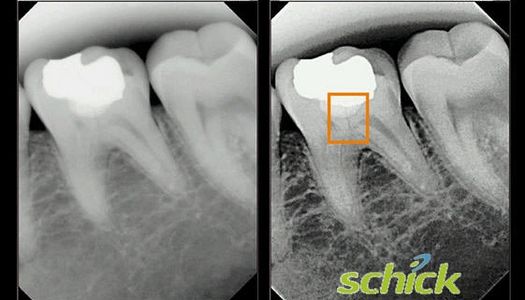

High definition digital x-ray sensors have far less radiation levels over that of film, and these special sensors provide even more detail than ever before... allowing us to see even the tiniest fracture or decay.

Check out the yellow square on the image showing the tiny fracture in this tooth that would otherwise go undetected!